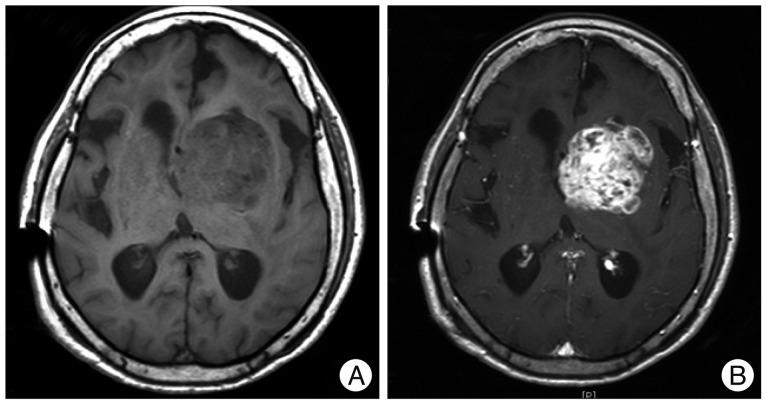

Here, we report a rare case of an anaplastic astrocytoma masquerading as a hypertensive basal ganglia hemorrhage. A 69-year-old woman who had been under medical management for hypertension during the past 3 years suddenly developed right hemiparesis with dysarthria. Brain computed tomography (CT) scans with contrast and CT angiograms revealed an intracerebral hemorrhage (ICH) in the left basal ganglia, without an underlying lesion. She was treated conservatively, but underwent a ventriculoperitoneal shunt operation 3 months after the initial attack due to deteriorated mental status and chronic hydrocephalus. Three months later, her mental status deteriorated further. Magnetic resonance imaging (MRI) with gadolinium demonstrated an irregular enhanced mass in which the previous hemorrhage occurred. The final histological diagnosis which made by stereotactic biopsy was an anaplastic astrocytoma. In the present case, the diagnosis of a high grade glioma was delayed due to tumor bleeding mimicking hypertensive ICH. Thus, a careful review of neuroradiological images including MRI with a suspicion of tumor bleeding is needed even in the patients with past medical history of hypertension.

在此,我们报告一例罕见的间变性星形细胞瘤,其临床表现类似高血压性基底节出血。一名69岁女性,在过去3年中一直接受高血压治疗,突然出现右侧偏瘫伴构音障碍。增强脑计算机断层扫描(CT)和CT血管造影显示左侧基底节区脑出血(ICH),无潜在病变。她接受了保守治疗,但在初次发病3个月后,由于精神状态恶化和慢性脑积水,接受了脑室腹腔分流手术。3个月后,她的精神状态进一步恶化。钆增强磁共振成像(MRI)显示在先前出血部位有一个不规则强化肿块。立体定向活检的最终组织学诊断为间变性星形细胞瘤。在本病例中,由于肿瘤出血酷似高血压性ICH,高级别胶质瘤的诊断被延迟。因此,即使是有高血压病史的患者,也需要仔细复查包括MRI在内的神经放射影像,以怀疑肿瘤出血。